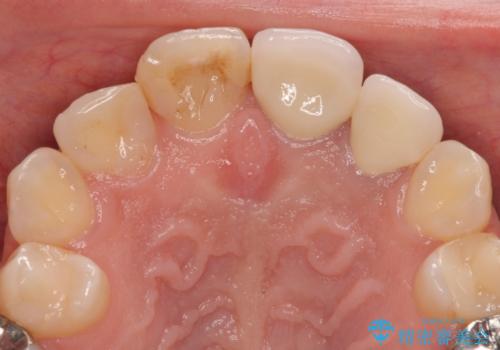

痛みが改善したことを確認した上で、オールセラミッククラウンにて補綴治療を行うこととしました。

歯根端切除から2週間を経過した時点で痛みは全くなくなっており、処置から6ヶ月後に撮影したレントゲン写真では炎症で吸収していた骨が回復している様子が確認されました。